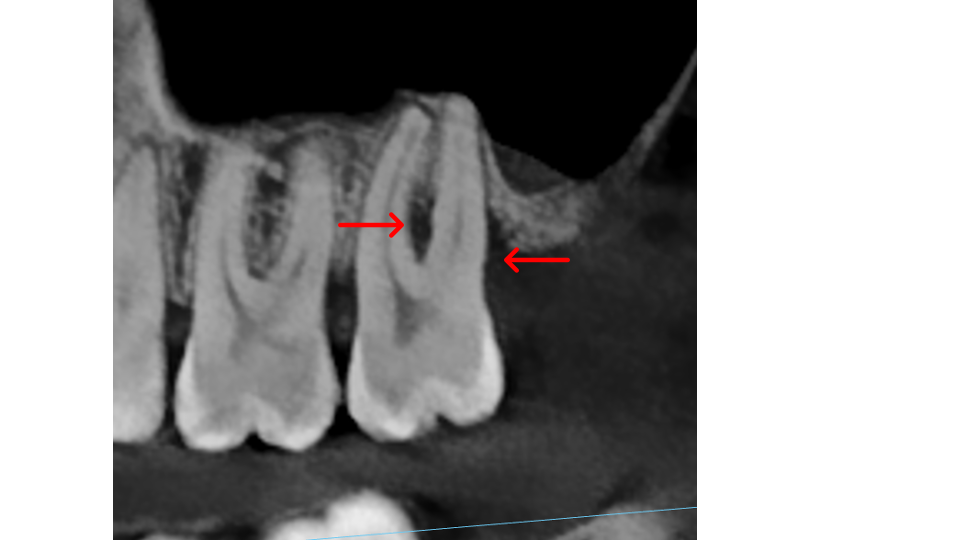

Furcations: This is the area where the roots of a multi-rooted tooth divide. Lower molars have one furcation (two roots); upper molars have three furcations (three roots). When bone loss reaches the furcation, disease spreads through the tooth, not just around it, creating undercuts that trap bacteria and make the area extremely difficult to clean without surgical access.

Bone thickness and shape: Bacteria on your teeth can only cause bone destruction within about 1.5 mm of where they sit, referred to as their "sphere of influence." When the surrounding bone is thin or roots are very close together, bacteria can destroy the bone completely, leading to gum recession and more exposed tooth surface. In these cases, non-surgical therapy is often sufficient. When bone is thick, bacteria can only destroy part of it, creating craters or "moats" around the tooth. These craters cannot be fully cleaned with non-surgical treatment and typically require surgery to correct.

- X-Rays (Radiographs): X-rays show the pattern and extent of bone loss. We can see whether bone has been lost evenly (horizontal loss) or whether craters and vertical defects have formed. This pattern directly determines which type of treatment you need.